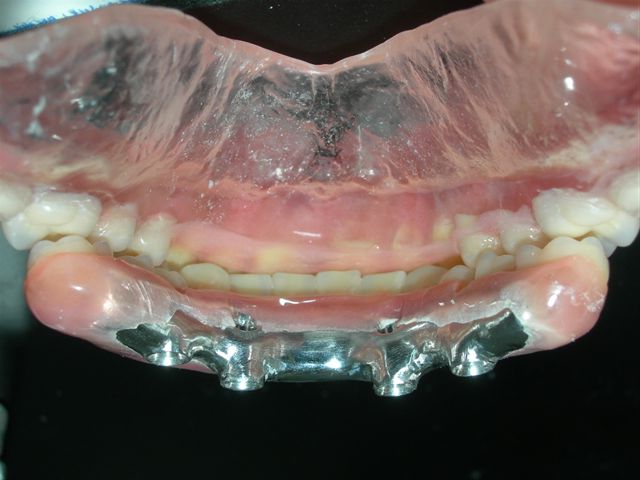

Protocolo acrilizada (VISTA SUPERIOR) |

Protocolo acrilizada (VISTA INFERIOR) |